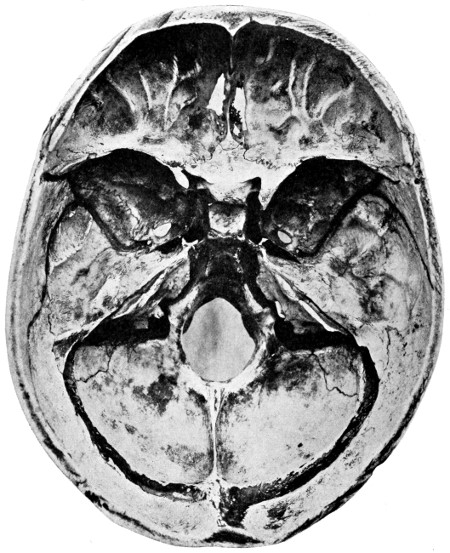

50 A and B. The inner aspect of the skull and the same seen on transillumination 137

51. To illustrate compression of the brain as produced by an extra-dural hæmorrhage from the middle meningeal artery[x] 141